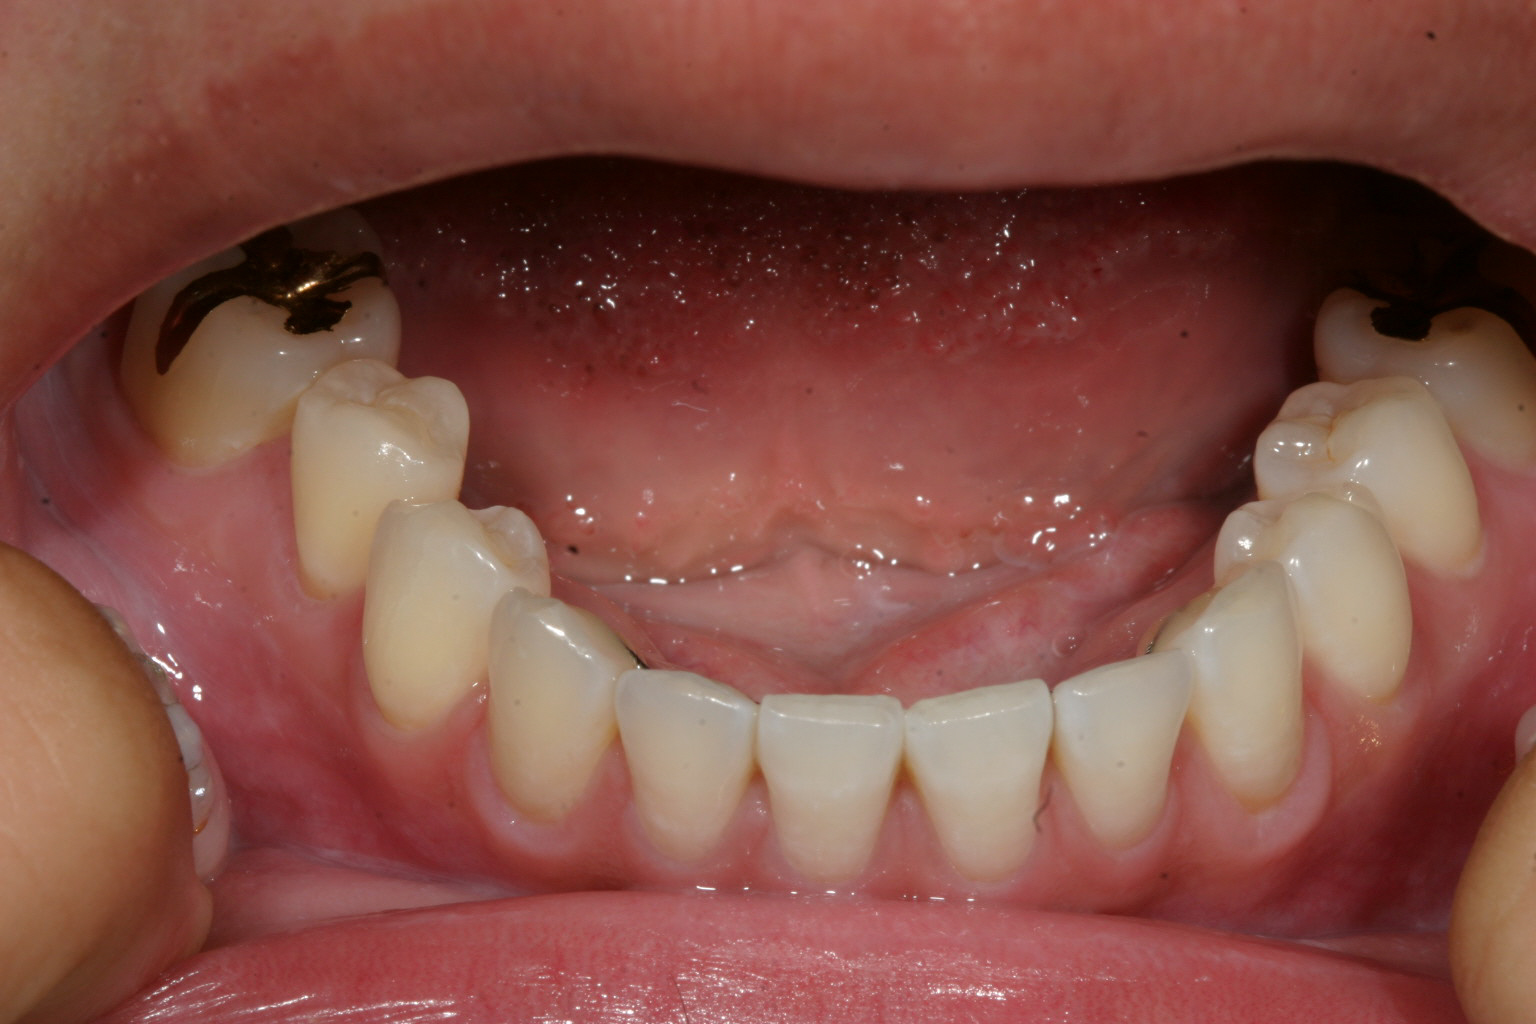

綺麗に並びましたね〜

下顎も改善しました。

噛み合わせもバッチリです。